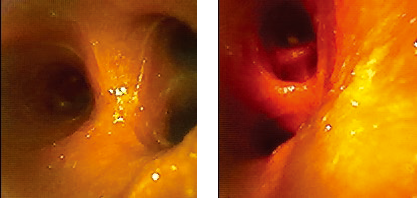

USHIO Theia-40 系列內(nèi)窺鏡系統(tǒng)及實(shí)際操作效果

內(nèi)窺鏡是一種精密的醫(yī)療檢查與治療工具,專(zhuān)門(mén)設(shè)計(jì)用于觀察人體內(nèi)部難以觸及的器官或組織狀況。其工作原理基于光學(xué)成像技術(shù):內(nèi)置的高亮度光源照亮待檢區(qū)域,鏡頭捕捉反射或散射的光線并形成圖像,這些圖像隨后通過(guò)光纖或電子傳輸系統(tǒng)傳送至外部顯示器,供醫(yī)生進(jìn)行細(xì)致的觀察與診斷。